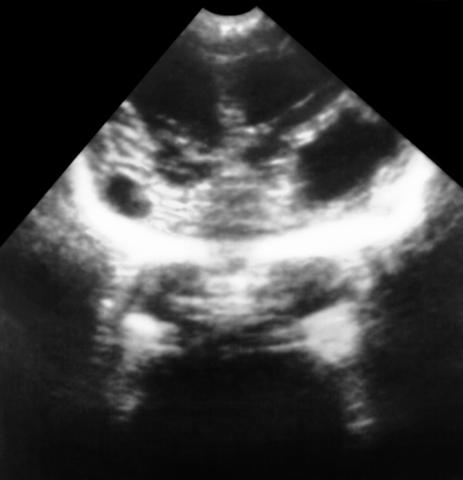

Рис. 2. Ультразвуковая картина головного мозга ребенка с множественными кистами на месте очагов кровоизлияний.